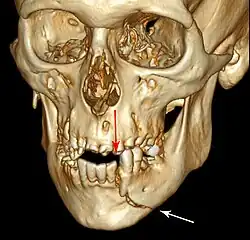

Injuries to supporting bone

This injury involves the alveolar bone and may extend beyond the alveolus.[5][6] There are five different types of alveolar fractures:

- Fracture of the maxilla: Le Fort fracture, zygomatic fracture, orbital blowout

Trauma injuries involving the alveolus can be complicated as it does not happen in isolation, very often presents along with other types of tooth tissue injuries.

Signs of dentoalveolar fracture:

Investigation: Require more than one radiographic view to identify the fracture line.

Treatment: Reposition displaced teeth under local anaesthetic and stabilise the mobile segment with a splint for 4 weeks, suture any soft tissue lacerations.